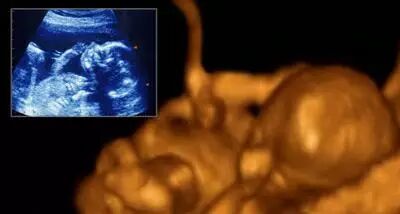

三个月:

胎儿的身体为7-9厘米,体重约20克,重要的是已长出鼻子、嘴唇四周、牙根和声带等,和以前比,更象人脸了,眼睛上已长出眼皮。